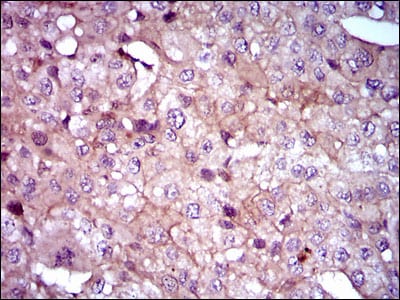

分类: 科研抗体货号: 30406别名: ANX1; LPC1应用: WB,IHC反应种属: Human,Mouse,Monkey